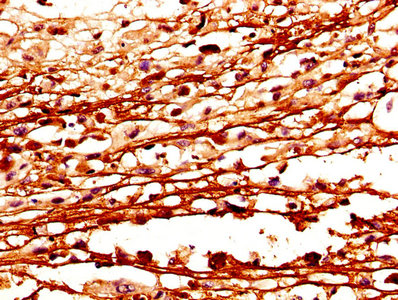

IHC image of CSB-PA006099DA01HU diluted at 1:400 and staining in paraffin-embedded human melanoma performed on a Leica BondTM system. After dewaxing and hydration, antigen retrieval was mediated by high pressure in a citrate buffer (pH 6.0). Section was blocked with 10% normal goat serum 30min at RT. Then primary antibody (1% BSA) was incubated at 4°C overnight. The primary is detected by a biotinylated secondary antibody and visualized using an HRP conjugated SP system.